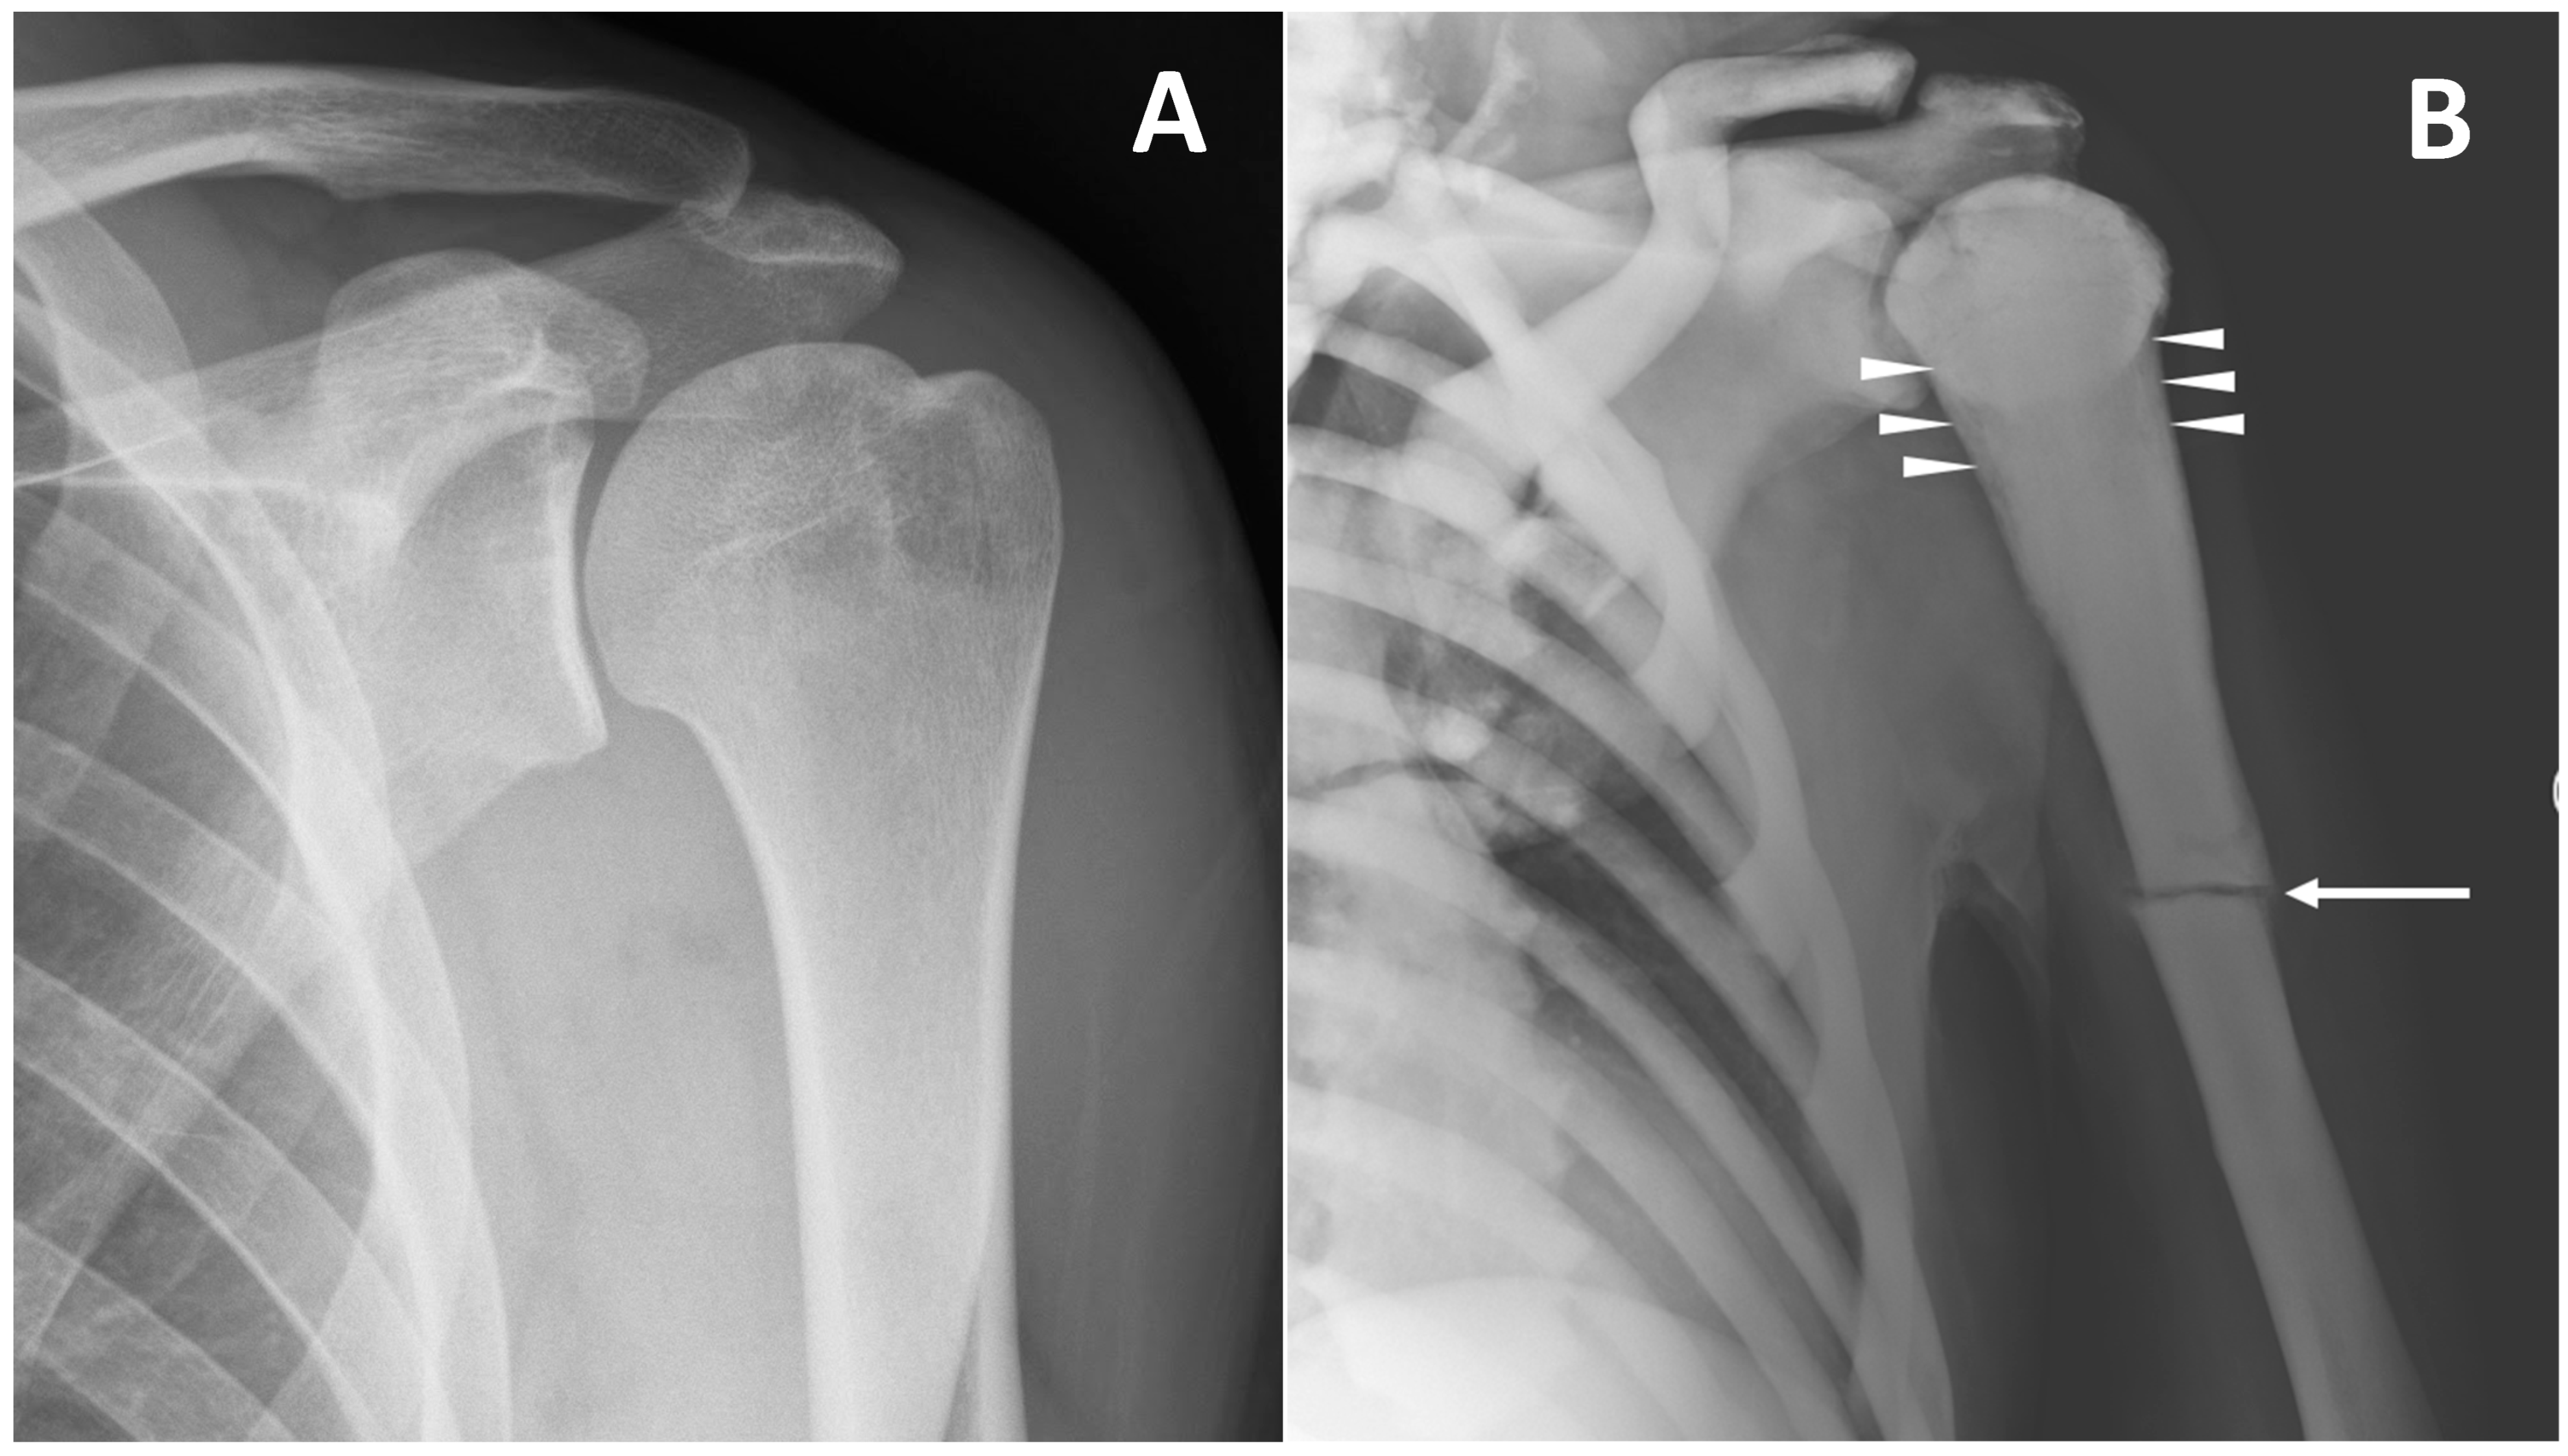

Imaging tools are also fundamental for the identification and assessment of complications. Above all complications, pathological bone fractures are the most common ones, and can be found differently in all osteopetrosis subtypes (Figure 5).

Figure 5. (A) conventional radiography of the left shoulder in a young healthy male (shown as comparison). (B) conventional radiography of a 45-year-old male with ARO type of osteopetrosis presenting with atraumatic pathological fracture of the diaphysis of the left humerus (arrow). A mild alteration of proximal metaphysis shape (arrowheads), and a diffuse increase in bone density of all the skeletal sites included can also be detected.